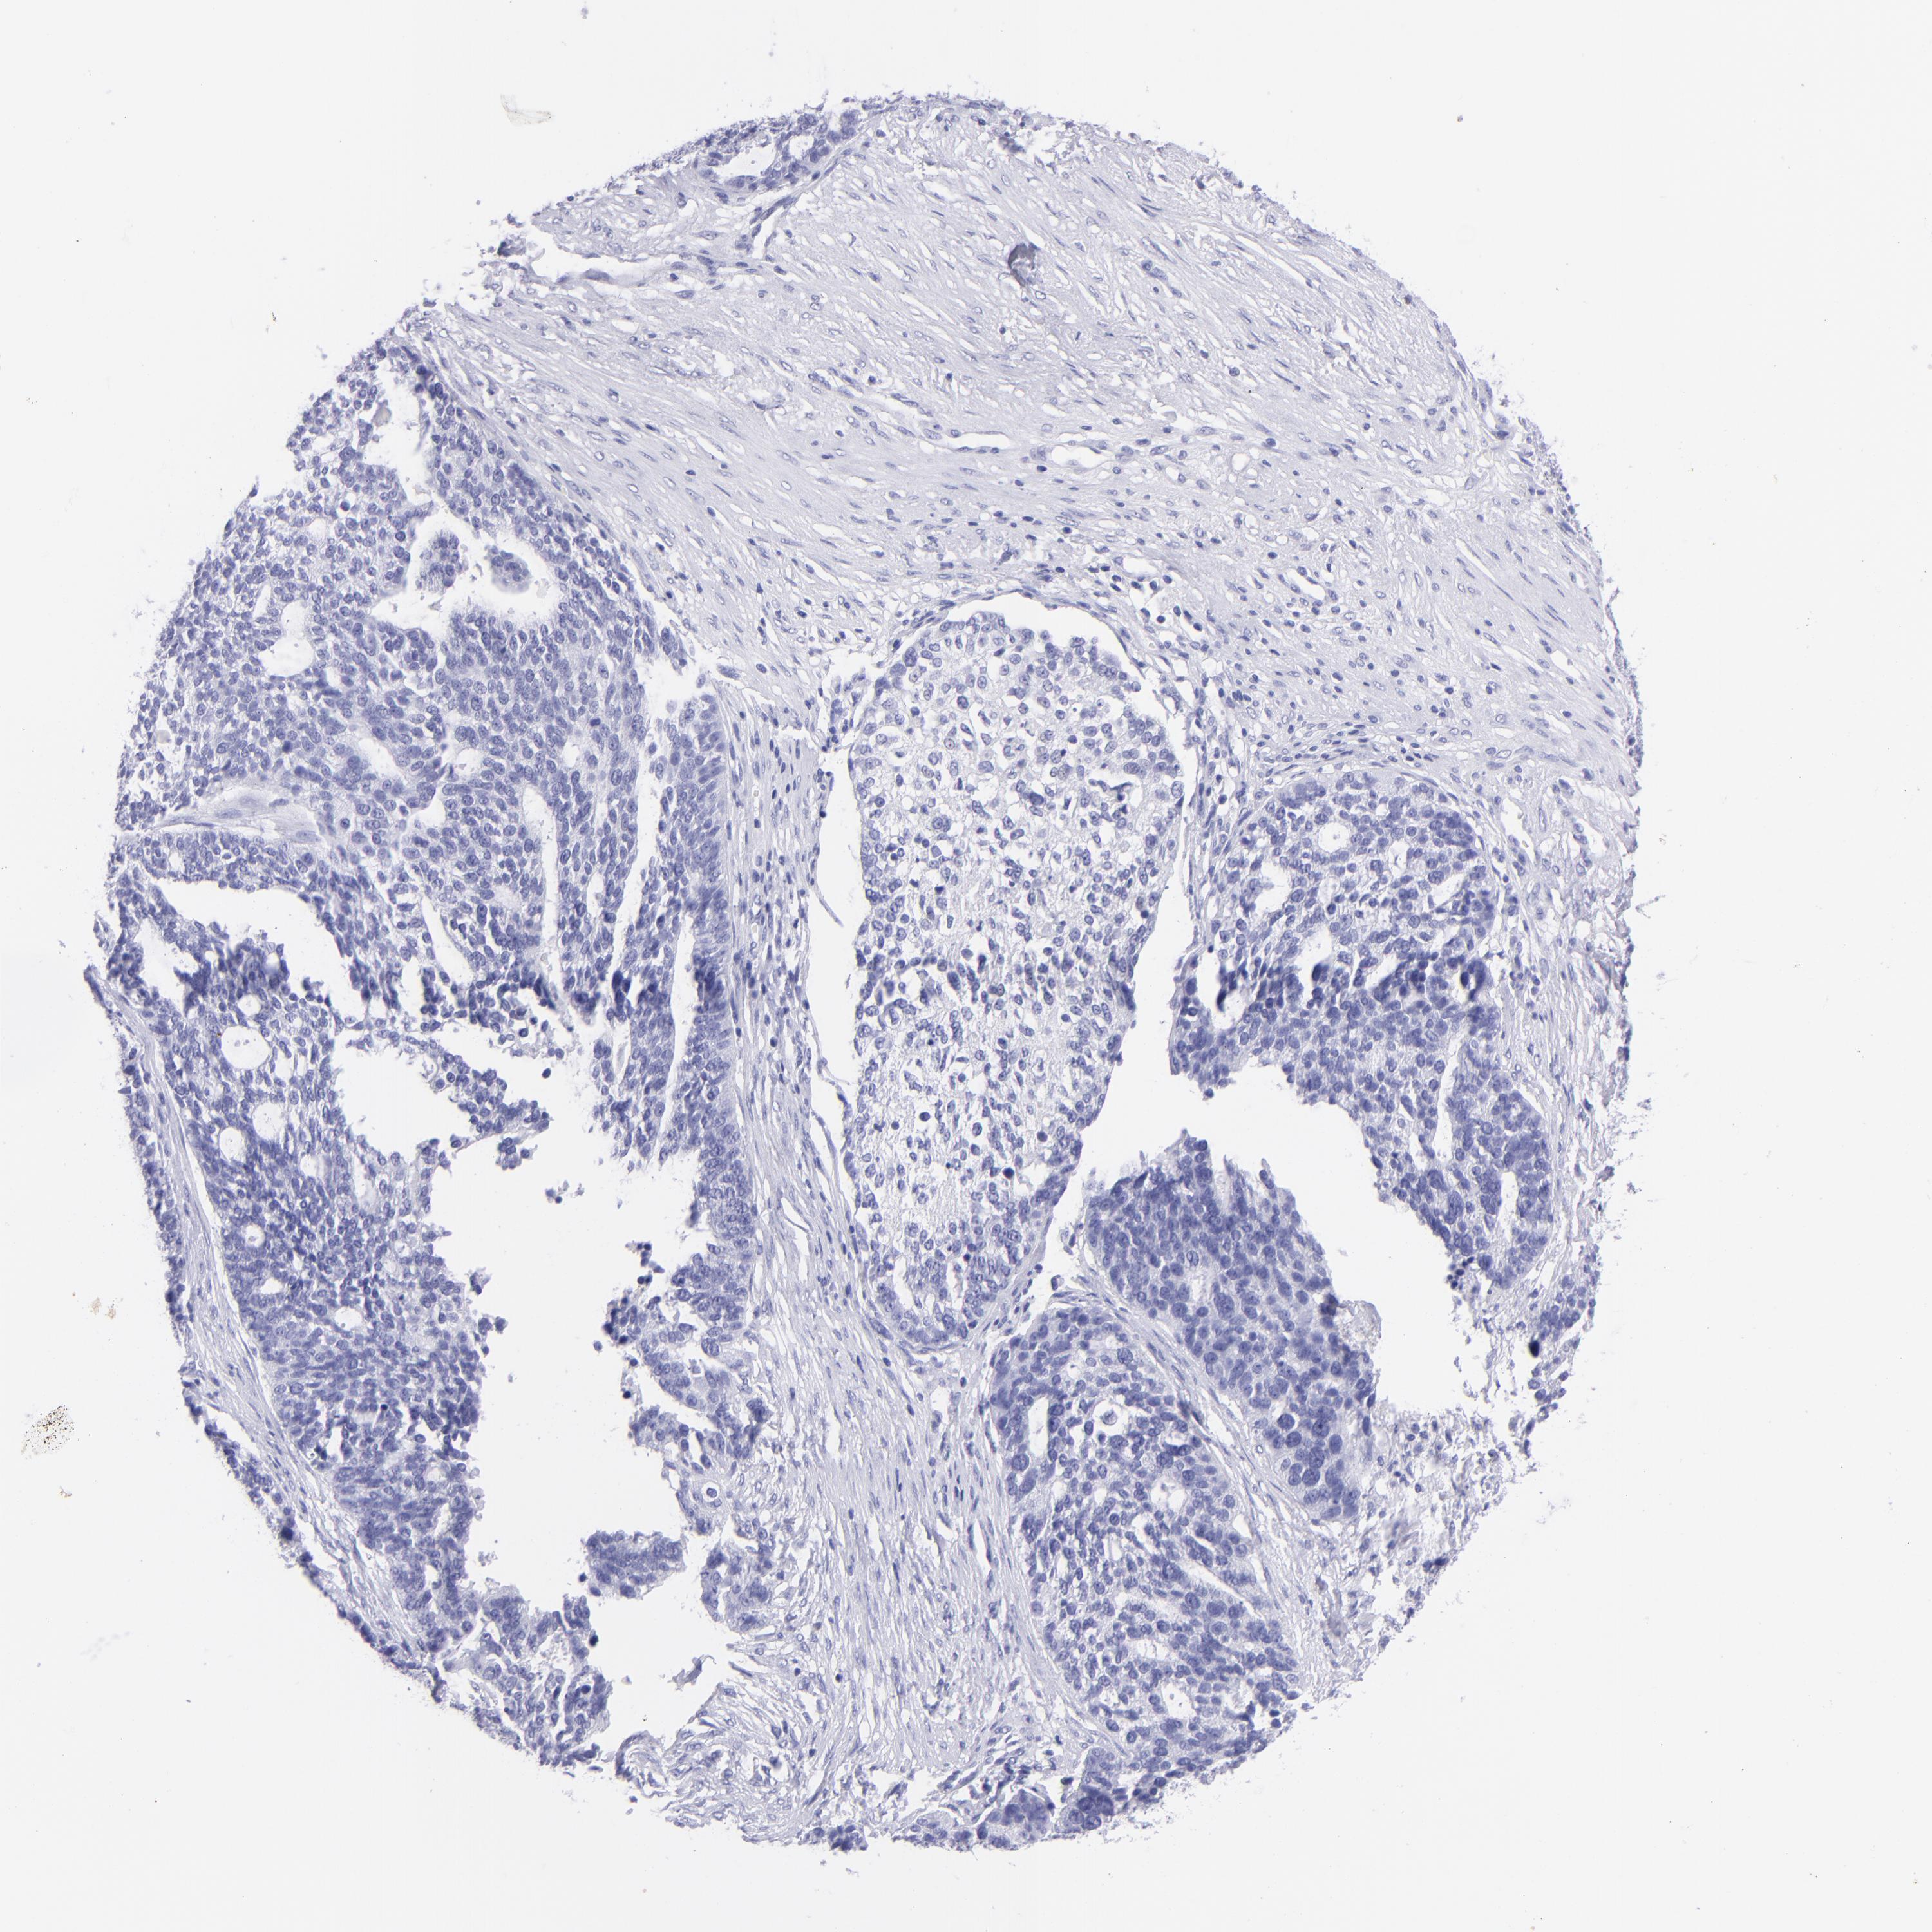

OVARIAN CANCER - Protein expressioni

A mouse-over function shows sample information and annotation data. Click on an image to view it in a full screen mode. Samples can be filtered based on level of antibody staining by selecting one or several of the following categories: high, medium, low and not detected. The assay and annotation is described here.

Note that samples used for immunohistochemistry by the Human Protein Atlas do not correspond to samples in the TCGA dataset.

Antibody stainingi

Antibody staining in the annotated cell types in the current human tissue is reported as not detected, low, medium, or high, based on conventional immunohistochemistry profiling in selected tissues. This score is based on the combination of the staining intensity and fraction of stained cells.

Each image is clickable and will lead to virtual microscopy that enables deeper exploration of all samples and also displays staining intensity scores, fraction scores and subcellular localization as well as patient and tissue information for each sample.

Antibody HPA009177

Antibody CAB002661

Staining

High

Medium

Low

Not detected

Intensity

Strong

Moderate

Weak

Negative

Quantity

>75%

75%-25%

<25%

None

Location

Nuclear

Cytoplasmic/membranous

Cytoplasmic/membranous,nuclear

Cystadenocarcinoma, serous, NOS

Carcinoma, endometroid

Cystadenocarcinoma, mucinous, NOS

Carcinoma, NOS